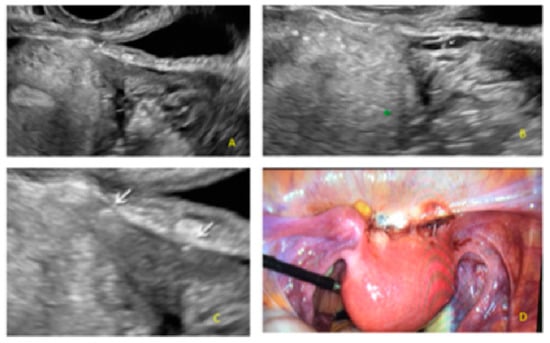

- The presence of hypoechogenic associated tissue (hypoechoic areas surrounding a small cyst area; we called this a “hat”). This tissue does not protrude or invaginate the peritoneal surface.

- The lesion may be convex, protruding from the peritoneal surface into the peritoneal cavity (we called this “bulging”), or it may appear as a concave defect in the peritoneum (we called this a “pocket”).

- The presence of hyperechoic foci (we called this a “pearl”).

- The presence of velamentous (filmy) adhesions associated to the lesion (we called this a “veil”).